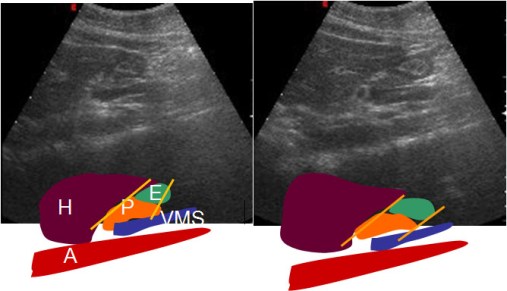

El desplazamiento del estómago (que desciende en la inspiración) con respecto al páncreas (órgano retroperitoneal inmóvil con la respiración) es un hallazgo normal. Éste, pues, es uno de los pocos signos radiológicos que representan un hallazgo normal.

La presencia de este signo excluye invasión pancreática en pacientes con carcinoma gástrico. Los esquemas ilustran el desplazamiento normal. H: hígado. E: estómago. P: páncreas. VMS: vena mesentérica superior. A: aorta.

Lim, HK y cols: Assessment of pancreatic invasion in patients with advanced gastric carcinoma: usefulness of the sliding sign on sonograms. AJR 1999; 172: 615-618.